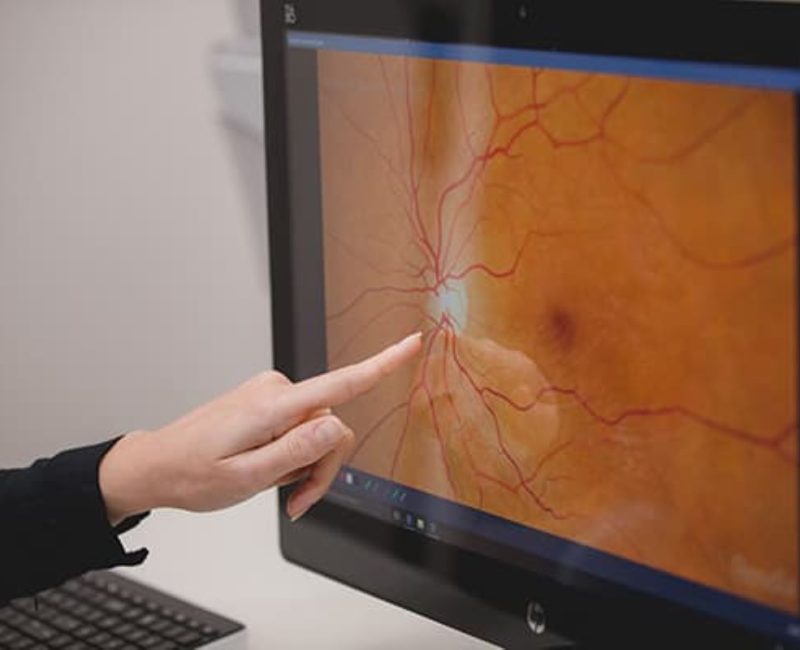

Diagnostic accuracy is critical in neuro-ophthalmology. Dr. Berman utilizes state-of-the-art technology and his extensive fellowship training to bridge the gap between neurology and ophthalmology, ensuring you receive a precise diagnosis and effective management plan.